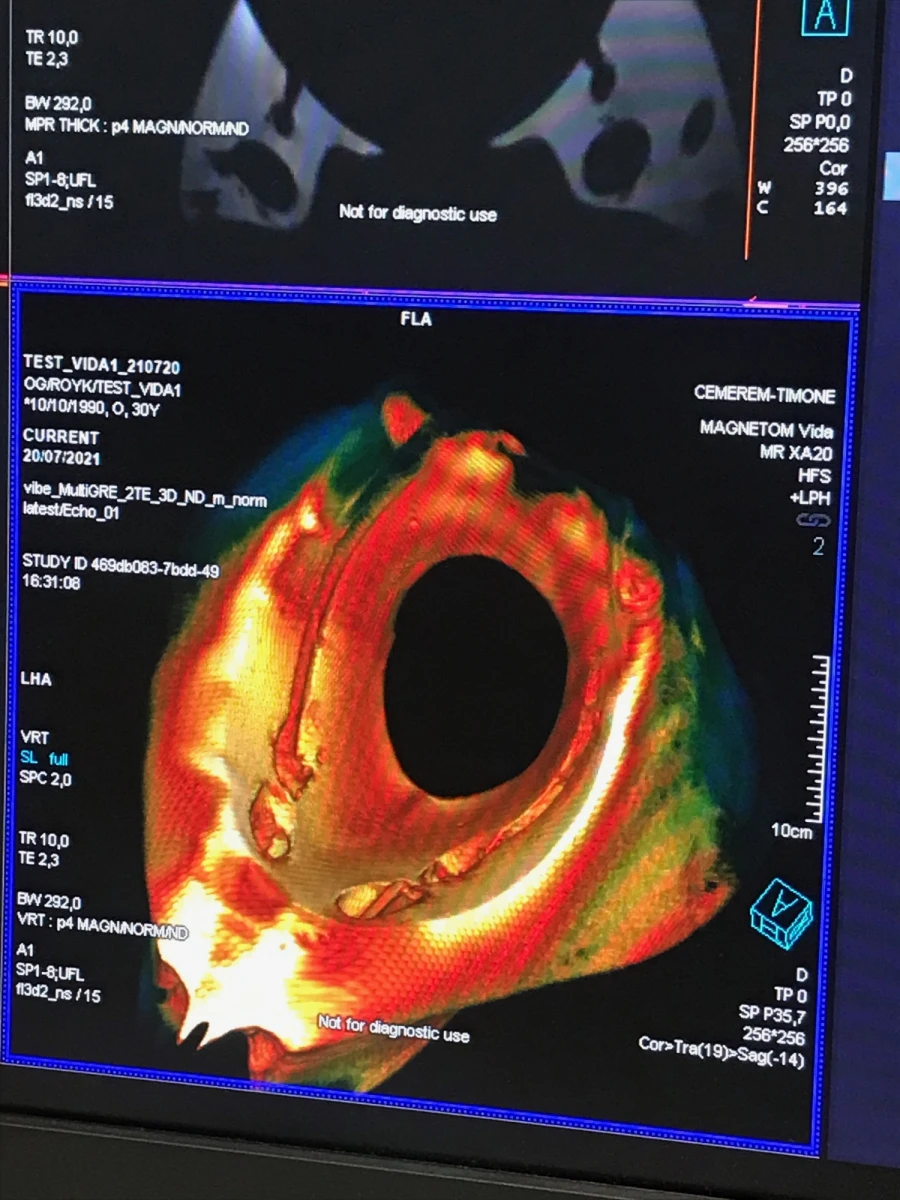

Inspirées par l’histoire des sciences anatomiques, Bulk flesh Studies se concentrent sur la manière dont les outils d’observation scientifique influencent et transforment notre perception du corps, de son existence à sa mort. Développé́ en collaboration avec un institut spécialisé (CRMBM à Marseille), le projet utilise les dernières technologies d’imagerie médicale IRM pour interroger notre incapacité à produire une image complète du corps compris comme et dans un environnement. La première phase du projet se développera entre deux espaces : à Jeanne Barret puis Buropolis et le laboratoire du CRMBM. Différents assemblages composés de matériaux organiques, minéraux et synthétiques (plâtre, feutre, bois, élastomère, cire) seront créés dans l’atelier puis testés au centre d’imagerie médicale. À partir de ces tests, un ensemble de sculptures sera réalisé à l’échelle des outils d’observation avant d’être scanné. (…)